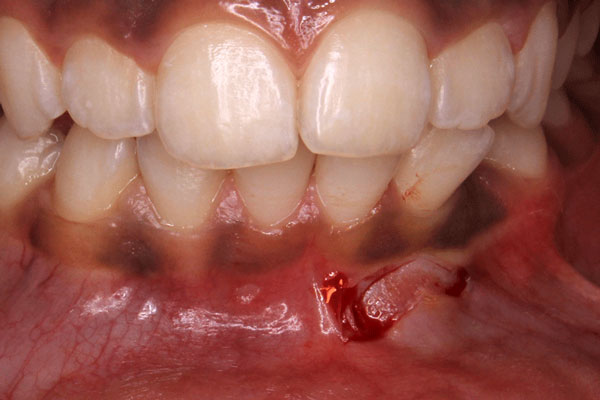

Disimpaction of Impacted canine

Disimpaction of Impacted canine

Disimpaction of Impacted canine

Disimpaction of Impacted canine

Disimpaction of Impacted canine

Disimpaction of Impacted canine

Disimpaction of Impacted canine

Disimpaction of Impacted canine

Disimpaction of Impacted canine

Disimpaction of Impacted canine

Disimpaction of Impacted canine

Disimpaction of Impacted canine

Disimpaction of Impacted canine

Disimpaction of Impacted canine

Disimpaction of Impacted canine

Disimpaction of Impacted canine